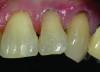

A 55-year-old woman presented with root decay along the left lateral incisor (tooth No. 10) and canine (tooth No. 11) (Figure 1). It was proposed that invisible Class V restorations be placed using an MMID procedure. There are several keys to attaining a successful invisible Class V restoration. Proper understanding of composite resin shade selection, preparation design, and sequence of composite resin layering are important to achieve an ideal blending of the composite resin to the existing tooth. Correct finishing and polishing technique is equally essential in obtaining a seamless esthetic restoration.3,11

Shade selection is always completed before initiating treatment; this is important to develop the proper shade-layering sequence. Composite shades were placed directly on the tooth and shades that matched the areas of the tooth being restored were chosen (Figure 2). To achieve an invisible Class V restoration, a more complex layering process is needed to blend the composite resin.

Total removal of the decay was performed. To keep the preparation minimally invasive, a caries indicator (Seek®, Ultradent Products, Inc., www.ultradent.com) was used so that only the infected dentin was removed. Minimally invasive burs (Micro Prep Kit, Komet USA, www.kometusa.com) were used, which are helpful when minimal tooth removal is an objective (Figure 3). A long-bevel margin (889M-007, Komet USA) was then created along the facial side so that the final composite resin could be blended to the existing dentition. A thin layer of resin-modified glass ionomer (RMGI) (GC Fuji II™ LC, GC America Inc.) was sculpted and light-cured to cover the affected dentin.

Before bonding, the enamel was etched with 37% phosphoric acid (ETCH-37™ 37% Phosphoric Acid Etchant, BISCO, Inc., www.bisco.com). A dentinal adhesive (ALL-BOND UNIVERSAL®, BISCO, Inc.) was placed, blown thin for 10 seconds with forceful compressed air, and then light-cured for 20 seconds (Figure 4). Using an injectable composite resin (G-ænial Universal Flo), a sequence of composite resin layering was performed to blend the composite resin to the existing tooth and create a natural polychromatic effect. To match the chromaticity along the gingival area, an opacious dentin shade, AO2, was bonded over the RMGI to mimic the lost dentin (Figure 5). Using a free-hand sculpt technique, universal shade A2 was injected over the opacious dentin composite resin with an emphasis on placing a convex anatomy to simulate natural dentition. Because of the chameleon effect and the depth of color of the body shade A2, no other shades were needed (Figure 6).

After final light-curing, esthetic contours were refined using aluminum oxide finishing discs (Sof-Lex™ Finishing Disc, 3M ESPE, www.3mespe.com) and Q-Finisher® composite resin finishing burs (H50AQ, Komet USA). Finally, microdiamond-infused polishing wheels and 1.0-µm microdiamond polishing paste brought out the surface luster of this injectable composite resin (Figure 7 and Figure 8). Using proper technique and state-of-the-art dental materials, natural color, contour, and finish to mimic tooth were achieved.12

CASE 1 INITIAL RESTORATION STEPS (1.) Extensive root decay along teeth No. 10 and No. 11. (2.) Composite resin try-in was done to develop final layering sequence. (3.) Teeth were isolated and minimally invasive preparations were completed with minimally invasive burs. (4.) After a thin liner of resin-modified glass ionomer was placed, dentinal adhesive was bonded to the root in preparation for composite placement. (5.) To match the chromaticity along the gingival aspect, an opacious dentin shade (AO2) was bonded over the resin-modified glass ionomer to mimic the lost dentin.

CASE 1 FINAL STEPS (6.) For final blending of this Class V restoration, a body shade of A2 was placed and blended to the enamel cavosurface. (7.) Preoperative view of Class V lesions on teeth No. 10 and No. 11. (8.) Postoperative final Class V restorations using modern minimally invasive dentistry techniques.